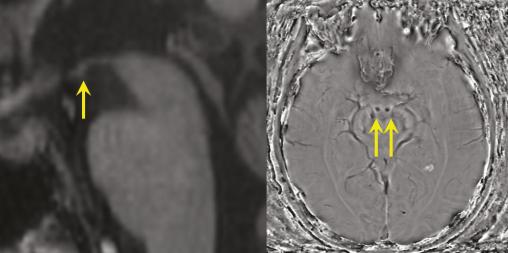

Anomalies observées dans un syndrome de Korsakoff (lié à une carence en vitamine B1).

À gauche  : IRM cérébrale en séquence T1, coupe sagittale passant sur les corps mamillaires. Nette atrophie du corps mamillaire (flèche).

À droite  : IRM cérébrale en séquence de susceptibilité magnétique. Nécrose hémorragique des deux corps mamillaires (flèches).